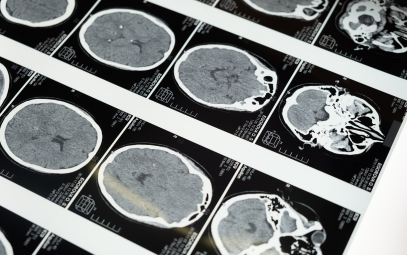

NEWS: Holding Prescribed Aspirin in Chronic SDH Receiving Burr Hole Evacuation May Not Decrease the Risk of Recurrent SDH Requiring Surgical Intervention at 6 Months

Written By: Shannon Hextrum, MD

Background: There is uncertainty regarding whether aspirin should be continued in patients with chronic subdural hematoma (cSDH) who undergo surgical evacuation. The risk of bleeding in the setting of aspirin use should be weighed against the risk of cardiovascular events in the setting of...